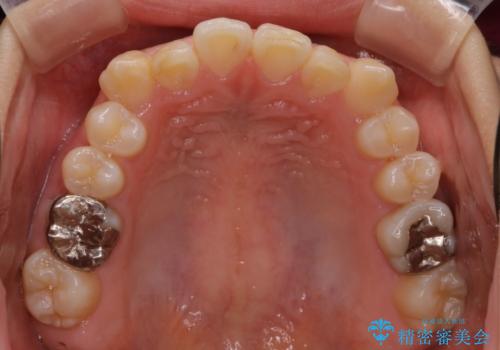

【ワイヤー矯正】前歯が出てるのをなおしたい。

- 前歯の凸凹を主訴に来院されました。

見た目だけではなくかみ合わせも良くなったと満足して頂きました。

治療後は見た目だけでなく、噛みやすくなったと満足していただけました。